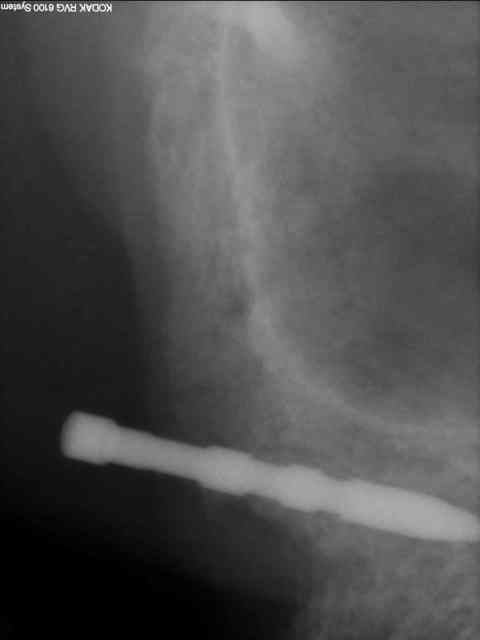

longer les parois antérieures des sinus à l'aveugle même après avoir étudié le scan...tu as fais des contrôles radios durant la phase de forage?

> longer les parois antérieurs des sinus à l'aveugle même après avoir étudié le

> scan...tu as fais des contrôles radios durant la phase de forage?

oui, c'est exactement ça .

d'abord un petit forage puis inclinaison et forage final.

je reconnais qu'il y a là une part de chance, je ne suis pas superman non plus.